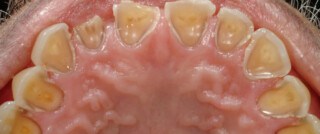

Teeth Erosion

Teeth erosion is a common dental problem that occurs when the outer layer of the teeth, called the enamel, gets worn away. Here are some facts about teeth erosion: Causes: Teeth erosion can be caused by various factors, including excessive consumption of acidic foods and drinks, frequent vomiting due to certain medical conditions like bulimia […]